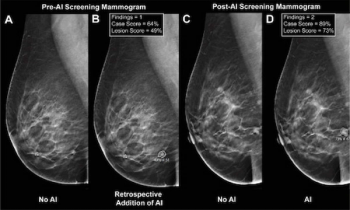

The use of AI software for digital breast tomosynthesis (DBT) facilitated a higher cancer detection rate and over double the PPV for exams with abnormal interpretation, according to a newly published study.

In a recent interview, Manisha Bahl, M.D., discussed key findings from a new study on AI and digital breast tomosynthesis that she presented at the Society for Breast Imaging (SBI) conference.